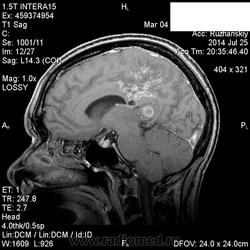

Мама приятельницы.Нарушение походки в течение 2-3 месяцев.

DDs: рассеянный склероз, токсоплазмоз, mts.

Рассеянный склероз вряд ли. Я бы добавила лимфому и глиобластому.

Думается больше о глиобластоме в форме бабочки. Из книги "Диагностическая нейрорадиология". Корниенко, Пронин.

На РС точно не похоже. Токсоплазмоз - навряд ли, т.к. "мама приятельницы", а это чаще всего бывает у ВИЧ-инфицированных.

+1 к глиобластоме.

Сегодня узнала: нейрохирурги за лимфому.Сделали КТ и подтвердили .

Сейчас  уточняют план лечения.

Пациенка умерла.

Месяца за 2 делали контроль-динамика отрицательная.